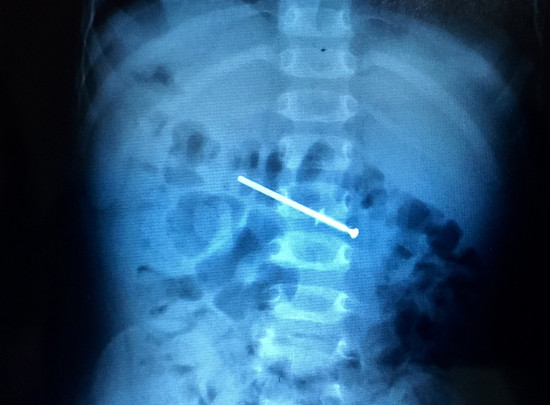

| Cây đinh được nhìn thấy qua phim X-quang. Ảnh: Thiên Chương |

Từ lời của gia đình, các bác sĩ đã chụp chiếu và phát hiện cây đinh vít nằm trong đường tiêu hóa. Việc phẫu thuật nội soi cho thấy dạ dày đã bị trầy xước, cây đinh lúc này đã chui xuống ruột non.

"Khoảng 10 phút sau khi dùng các vật dụng chuyên biệt, chúng tôi đã lấy thành công cây đinh bằng nhôm còn mới, dài khoảng 4,5 cm ra ngoài", bác sĩ Phạm Trung Dũng, Trưởng phòng nội soi, khoa Tiêu hóa, Bệnh viện Nhi đồng 1 cho biết.

Cũng theo bác sĩ Dũng, đối với trường hợp này, do cây đinh bén nhọn nên dị vật không thể thảy ra ngoài qua đường đi tiêu. Nếu nhập viện muộn, cây đinh kẹt ở tá tràng dễ gây thủng, xuất huyết và hoại tử.